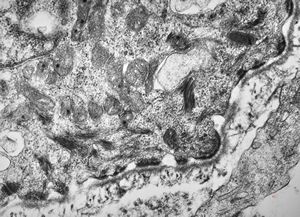

M,1y. | unusually cup-shaped mitochondria - plexus papilloma

M,1y. | intramitochondrial inclusion - plexus papilloma